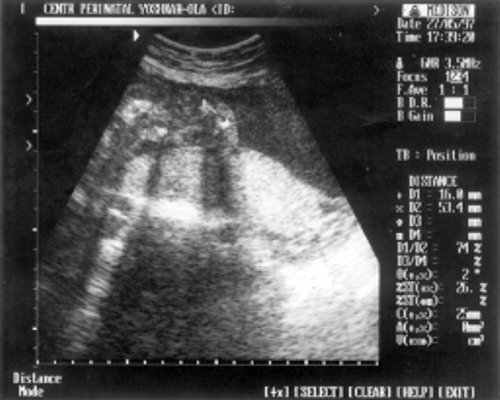

- ОкГрК (окружность грудной клетки) = 42 мм - 19,5 нед.

- ОЖ (окружность живота) = 182 мм - 22 нед. + 6 дн.

- ДБ (длина бедра) = 24 мм - 17 нед. (рис. 2)